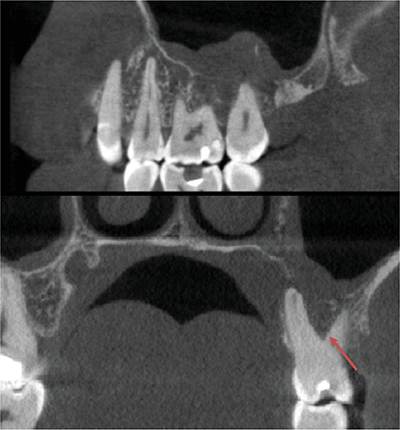

一名 47 岁的男性病史并无异常,因左上磨牙的非典型牙髓疼痛和治疗而转诊。临床和影像学检查发现,这些牙齿周围有一个广泛的、未定义的溶骨区。随后的骨活检诊断为弥漫大 B 细胞淋巴瘤,这是一种高级别非霍奇金淋巴瘤。血液科团队开出了六个周期的化疗处方,并辅以两个周期的甲氨蝶呤。医生应警惕非典型牙痛,考虑进行三维成像检查,以尽早排除恶性病变。教学要点:非典型牙痛应引起医生的警觉,并引导他们进行三维成像检查,以尽早排除恶性病变的诊断。

A 47-year-old male with an unremarkable medical history was referred for atypical endodontic pain and treatment of his left upper molars. Clinical and radiographic examinations revealed an extensive, undefined osteolytic area around these teeth. A subsequent bone biopsy diagnosed diffuse large B-cell lymphoma, a high-grade non-Hodgkin's lymphoma. The hematology team prescribed six cycles of chemotherapy, supplemented by two cycles of methotrexate. Practitioners should be alerted by atypical tooth pain to consider 3D imaging to exclude malignant pathology as early as possible. Teaching point: An atypical tooth pain should alert the practitioner and guide them towards 3D imaging to eliminate diagnostic of malignant pathology as early as possible.